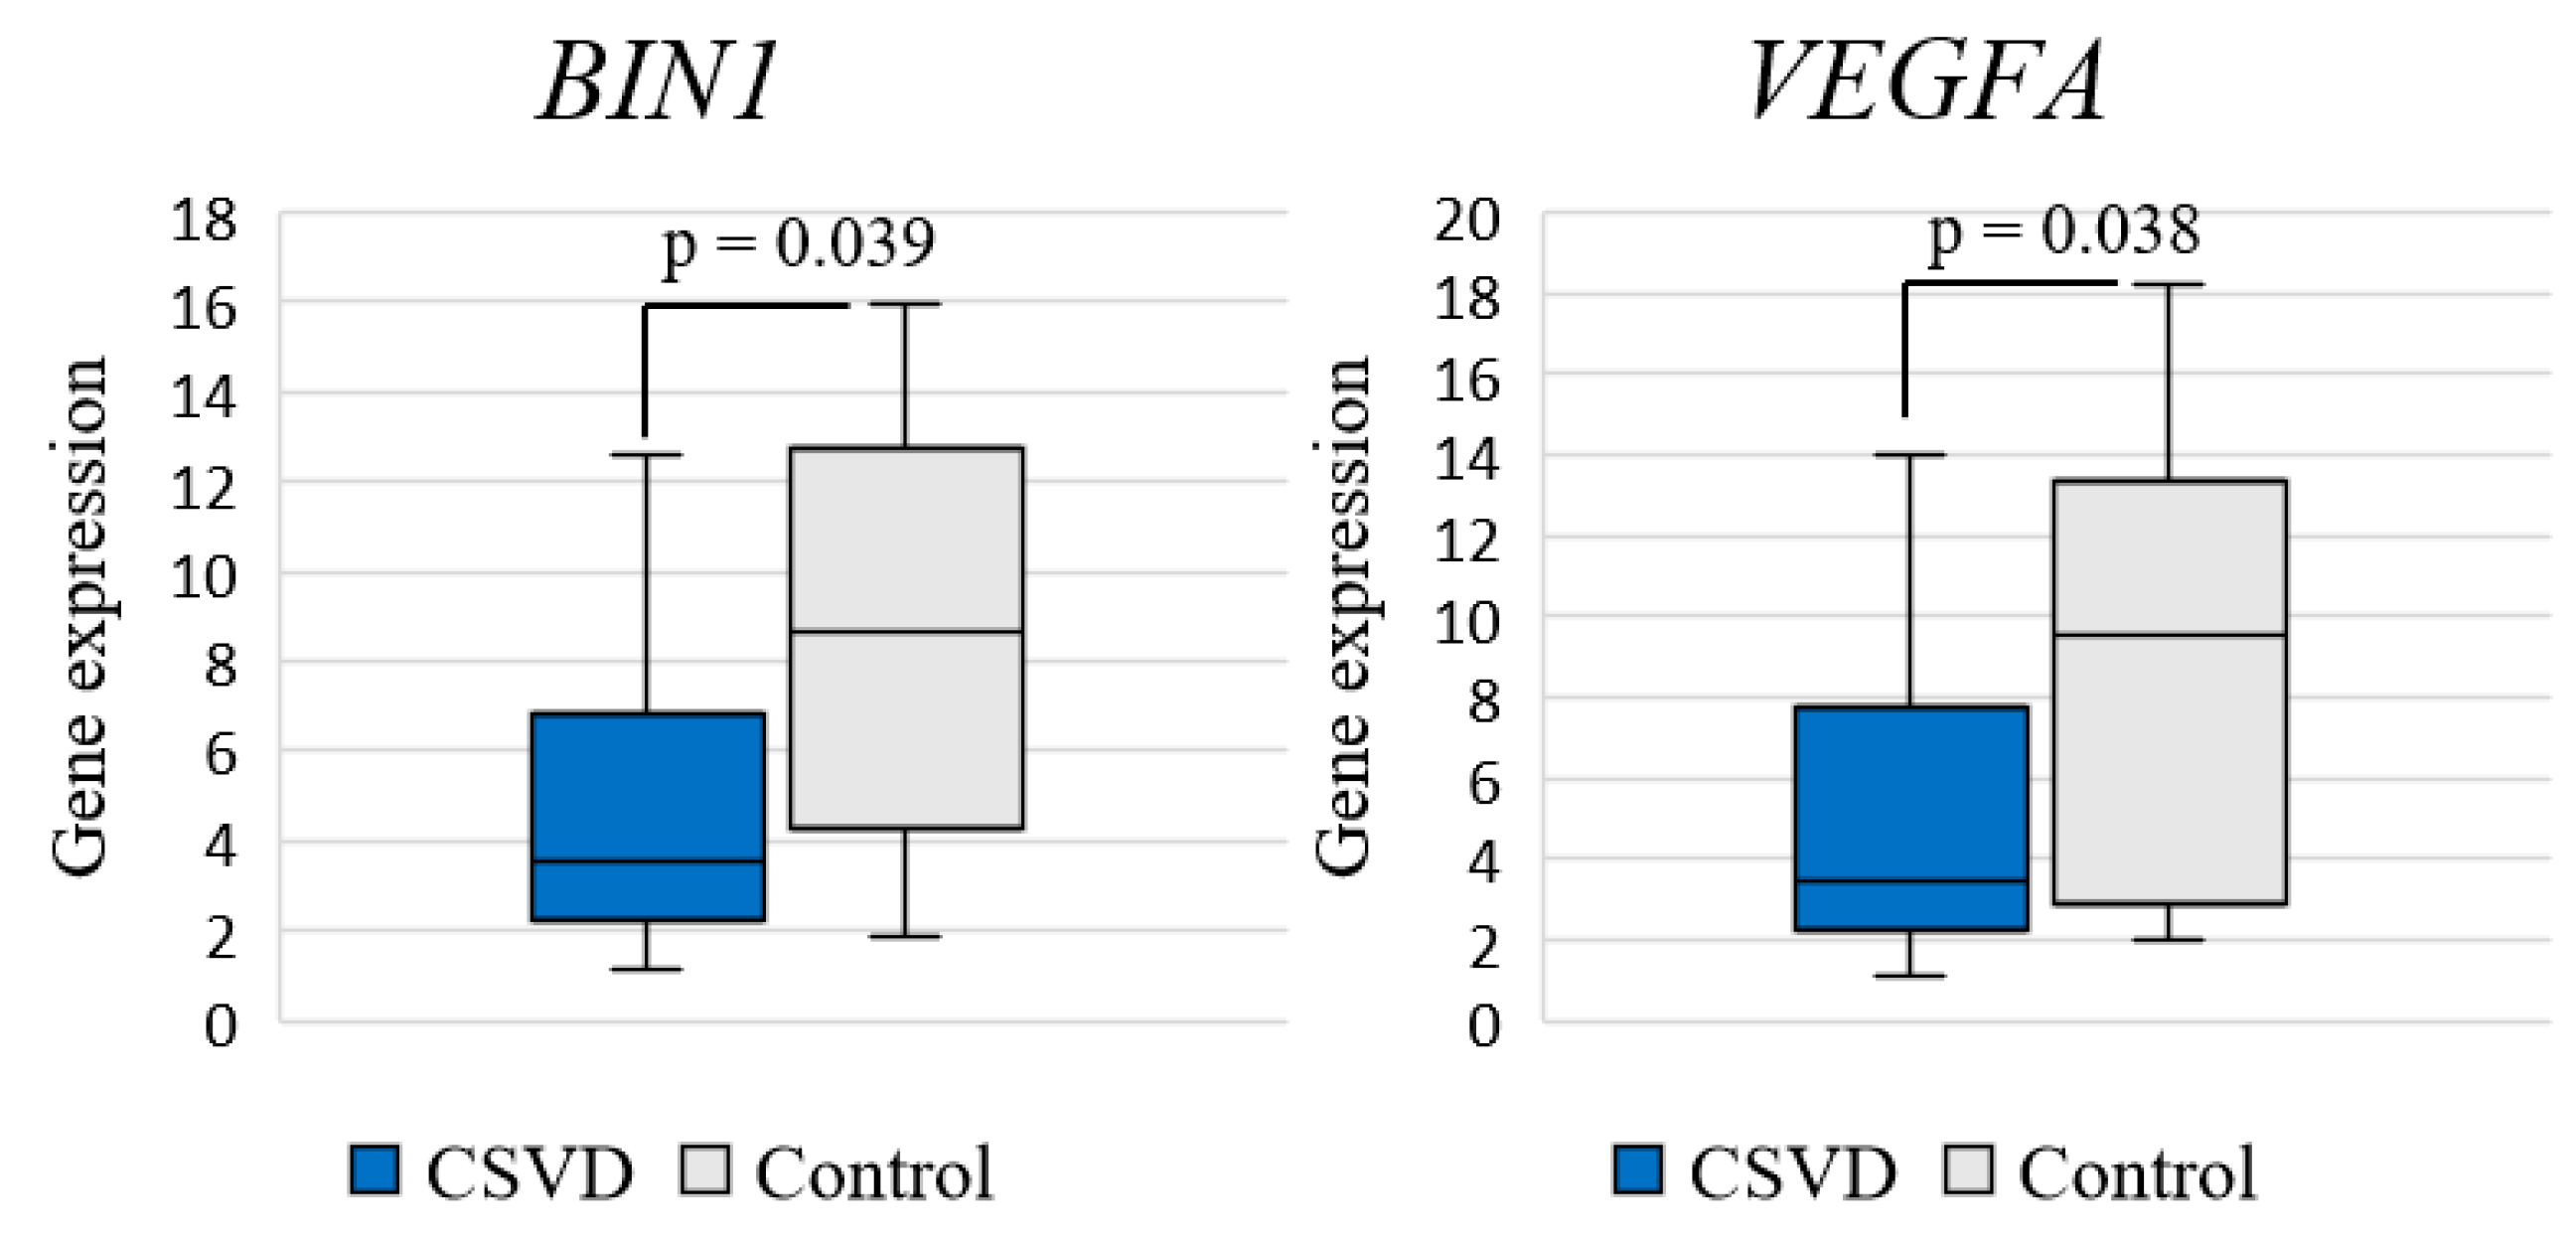

2.2. Expression of Inflammation-Associated Genes: CSVD Group vs. Control and MRI Types 1 and 2 CSVD vs. Control